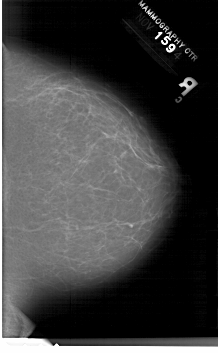

A_1202_1.RIGHT_MLO

RIGHT_CC LINES 6691 PIXELS_PER_LINE 4141 BITS_PER_PIXEL 12 RESOLUTION 43.5 NON_OVERLAY

RIGHT_MLO LINES 6661 PIXELS_PER_LINE 4321 BITS_PER_PIXEL 12 RESOLUTION 43.5 NON_OVERLAY